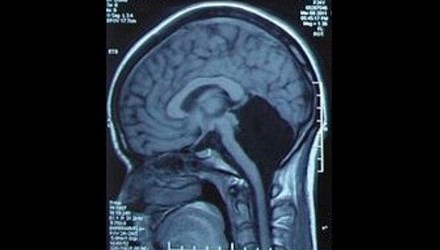

Một phụ nữ, 24 tuổi, ở tỉnh Quảng Đông, Trung Quốc phải nhập viện vì cảm thấy chóng mặt và buồn nôn. Sau khi chụp não, các bác sỹ của bệnh viện quân đội Quảng Đông hết sức ngạc nhiên khi phát hiện cô không có tiểu não (phần màu đen trong ảnh), tức là thiếu một nửa não bộ mà vẫn có thể sống bình thường.

Tiểu não nằm ở trung tâm hộp sọ, chứa khoảng một nửa số nơ ron thần kinh, khu vực chỉ huy việc cân bằng cơ thể, chạy nhảy, đá bóng và ngôn ngữ.

Do thiếu tiểu não nên đến 6 tuổi cô mới biết nói, 7 tuổi mới biết đi. Các cuộc kiểm tra cho thấy, cô có thể hiểu được các từ, nhưng gặp khó khăn khi phát âm, giọng của cô hơi run run và phát âm không được chuẩn.

Hiện cô đã có gia đình và có một con gái. Rất may cô bé có bộ não bình thường. Đây là một trong số 9 người trên thế giới mắc căn bệnh hiếm gặp này. Các bác sỹ tin rằng, các chức năng của tiểu não của cô có thể đã được thay thế bởi vỏ não.